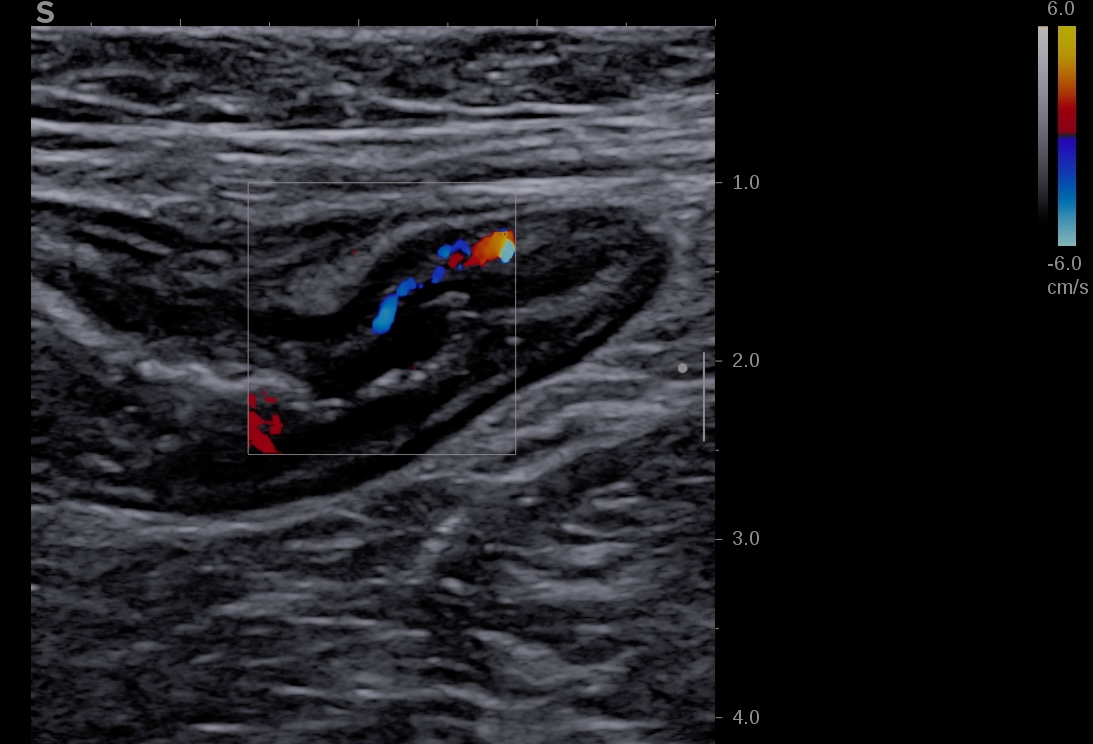

- Le Doppler Couleur (qui enregistre la direction des flux (rouge se rapproche de la sonde et bleu s'éloigne de la sonde)